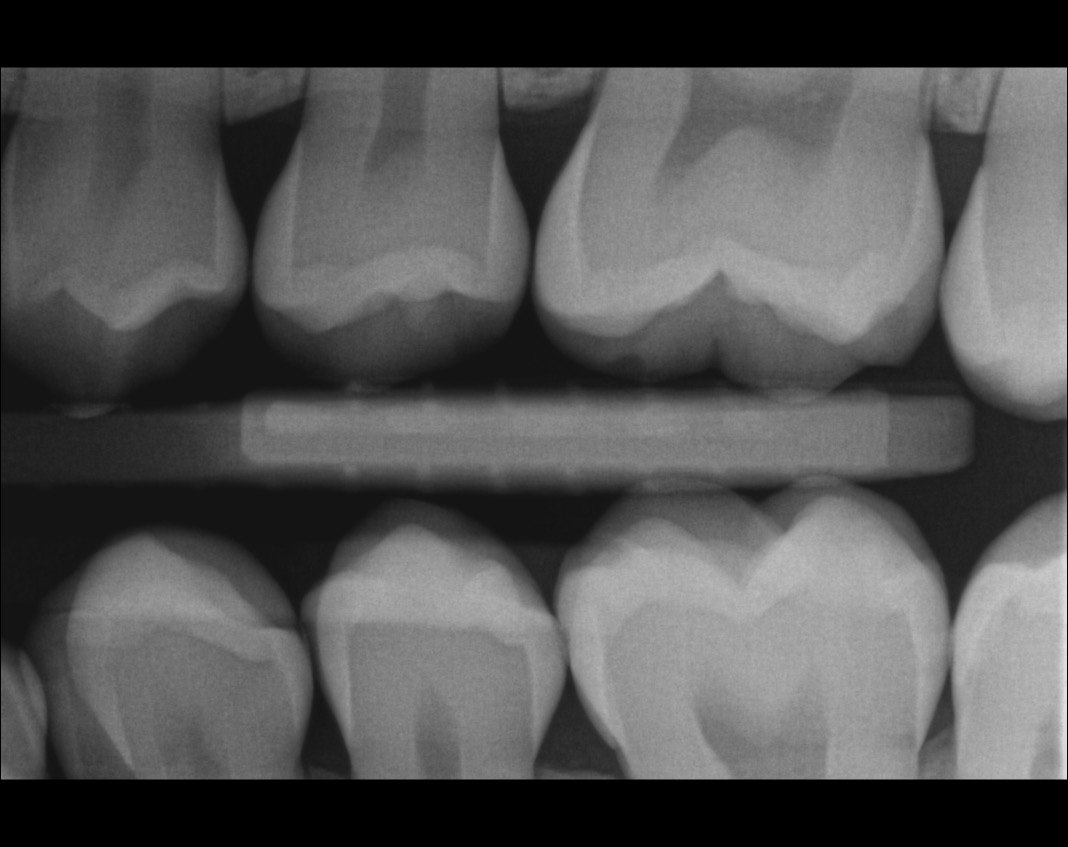

Question 26: What is the option explaining the distal surface of the tooth # 2.6 and mesial surface of the tooth # 2.7 respectively?

Question 27:  What is the option explaining the distal surface of the tooth # 2.5 and distal surface of the tooth # 2.4 respectively?

Question 28: What is the option explaining the distal surface of the tooth # 2.5?

Question 29: What is the option explaining the Mesial surface of the tooth # 2.5 and distal of tooth # 2.4 respectively?

Question 30: What option can be seen on the lower jaw of the following X ray?

Question 31: Which options can be selected for the following X ray?

Question 32: Which surface need restoration?

Question 33: What is the condition in mesial of tooth # 4.6?

Question 34: What is the level of caries on mesial of the tooth # 1.6?

Question 35: Which surface shows recurrent caries?

Question 36: What is the caries on distal surface tooth # 1.5?

37: What is the caries on mesial surface of tooth # 2.6 and distal surface of tooth # 2.5 respectivel?

38. What is the condition of the distal surface of tooth # 1.4 and mesial tooth surface tooth # 1.6?

39. What is the caries on distal tooth # 2.6 ?

40. What is the caries on mesial tooth #3.6 ?

41. What options can be selected for the following X ray?

42. What is the caries on mesial surface of the tooth # 3.6?

43. Which surfaces require restoration?

44. What is the condition on distal surface of the tooth # 4.4?

45. What is the condition on mesial surface of the tooth # 1.5?

46. which teeth shows evidece of occlusal recurrent caries?

47. Which option does not describe the X ray bellow correctly?

48. Which tooth shows recurrent caries?

49. Which surface shows a RA1 caries?

50. Which option is evident on the print of the X ray?